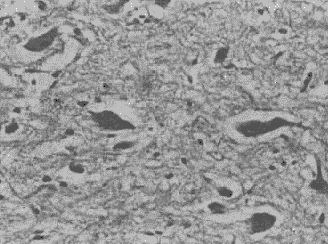

2.1.1 光镜观察 正常对照组和假手术组各时相点双侧大脑半球均可见散在的暗神经元和坏死神经元,但20个高倍视野的总数不超过10个。MCA闭塞 0.5小时,暗神经元和坏死神经元首先大量出现在缺血侧基底节区,并见完整神经元周围间歇增大、胶质水肿、炎细胞侵润。至MCA闭塞 1小时,这些改变才逐步扩展到皮质。基底节区的细胞损伤高峰期位于MCA闭塞 0.5小时至2小时,皮质为MCA闭塞 1小时至6小时,而双侧海马MCA闭塞 24小时内仅见散在极少量的暗神经元和坏死神经元分布,但病侧海马组织水肿持续存在,重于健侧。MCA闭塞 24小时后,海马的暗神经元和坏死神经元迅速增加,如表1所示。基底节区和皮质MCA闭塞24小时后逐渐出现盘状坏死(图1),而海马始终未见盘状坏死。

图1 MCA闭塞24小时,缺血侧基底节区切片。HE×400